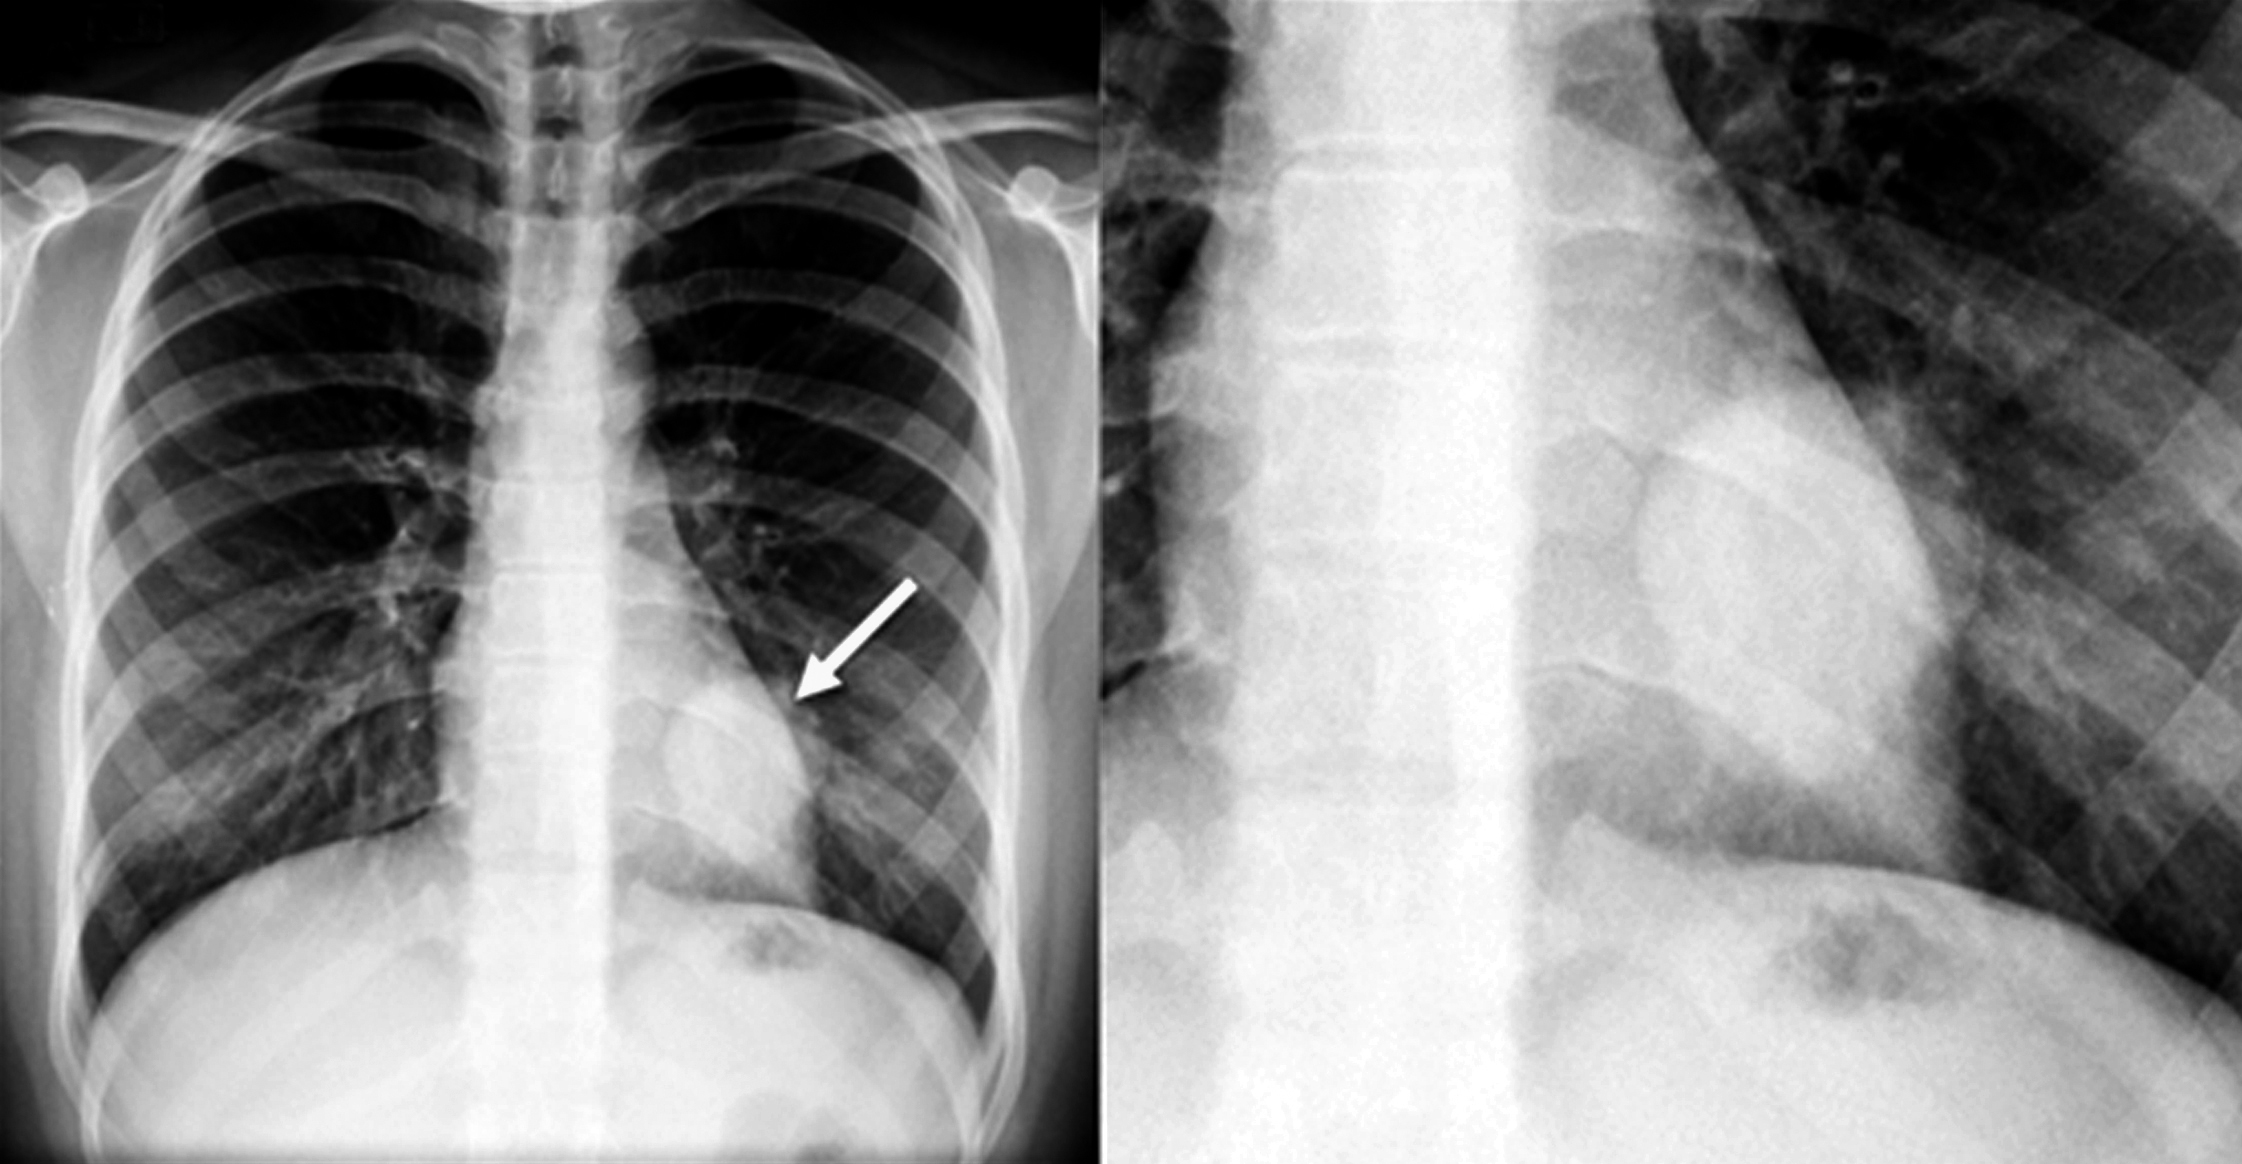

Se solicita radiografía de tórax de frente, en la cual se observa masa en tercio inferior de hemitórax izquierdo, retrocardíaca, redondeada, de bordes bien definidos, de aproximadamente 4 cm de diámetro. Resto del parénquima pulmonar y silueta cardiomediastínica sin alteraciones. (Figura 1)

Figura 1

Radiografía de tórax, proyección PA (a) y aumento del sector de interés (b). Se observa masa retrocardíaca en hemitórax izquierdo (flecha).